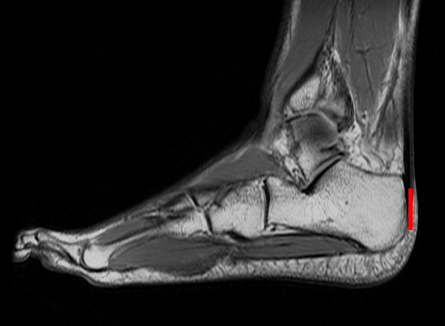

RUNNING HEEL An MRI of a distance runner’s foot and ankle shows a heel bone sized to pull the Achilles tendon taut, a condition that researchers say applied to Stone Age humans but not to Neandertals.